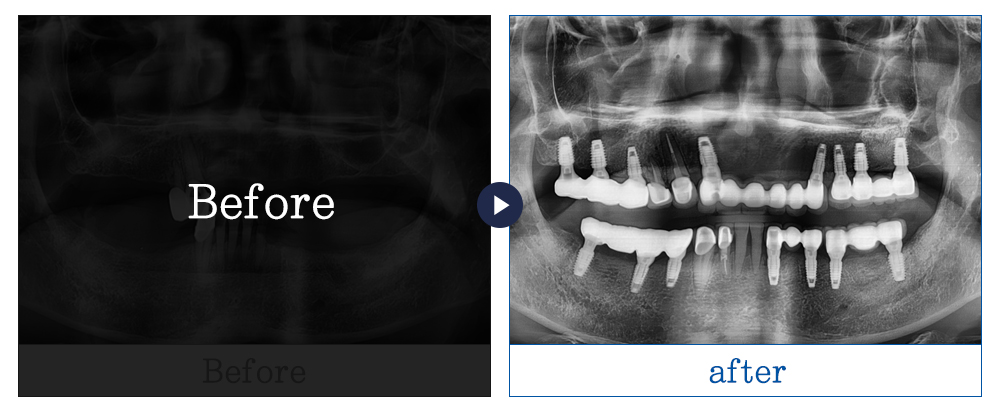

실제 본원에서 치료를 받은 환자의 동의를 얻어 게재하였으며 무단 복제, 사용을 금합니다.

부작용 고지 : 치료는 개인마다 차이가 있으며 치료 후 감염, 염증, 합병증 감각이상등의 부작용이 발생할 수 있습니다.

임플란트 사례